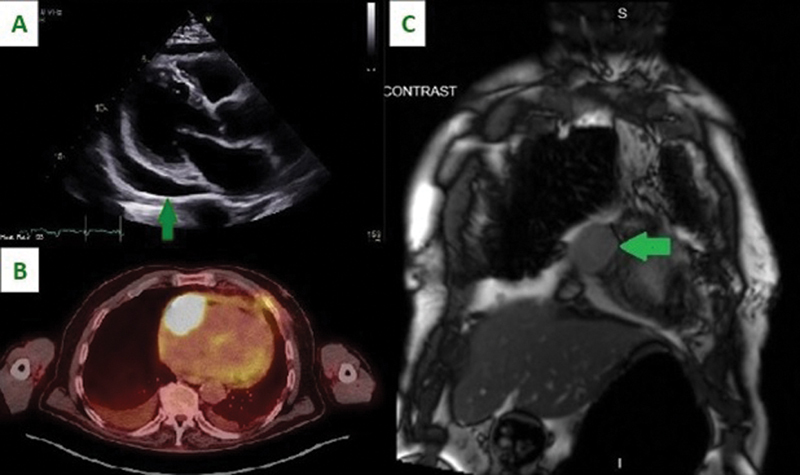

Background  Patients with primary cardiac tumors may present with symptoms based on the size and location of the tumor. Symptoms may include congestive heart failure secondary to intracardiac obstruction, systemic embolization, arrhythmias, and constitutional symptoms. Case Description  A patient presented with new onset atrial fibrillation and heart failure. Workup including open surgery revealed a primary cardiac lymphoma. Conclusion  Cardiac tumors present with a variety of symptoms and are best evaluated by echocardiogram, computed tomography angiography, and magnetic resonance imaging. Tissue diagnosis is necessary. Although primary cardiac lymphoma is rare, long-term survival after chemotherapy and rituximab is superior to other cardiac malignancies.